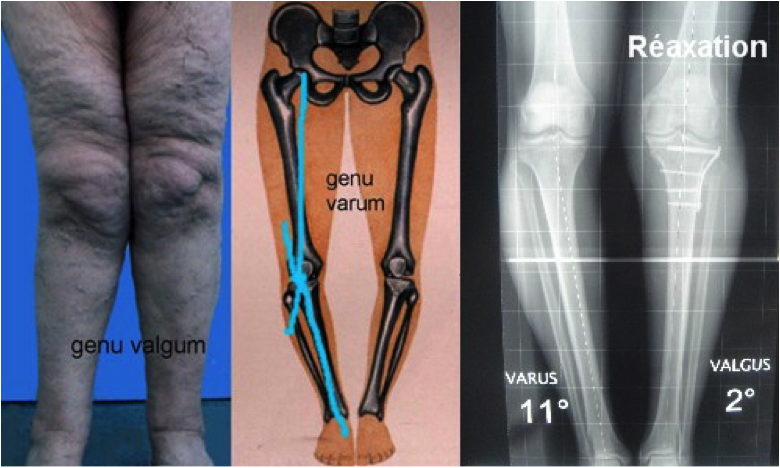

On retrouve certains facteurs favorisants comme l'hérédité (une augmentation d’1 point de l’Indice de Masse Corporelle - IMC - entraîne une majoration de 15% de survenue de l’arthrose), l'obésité, le sexe féminin (2% des hommes pour 6% des femmes à partir de 60 ans), le surmenage sportif ou une anomalie des axes entre le fémur et le tibia (genu varum ou genu valgum) ou entre le fémur et la rotule (dysplasie fémoro-patellaire).

La déformation : présente uniquement dans les arthroses évoluées, la déformation du membre inférieur est le troisième symptôme de la gonarthrose et correspond au début à l'usure cartilagineuse (en varus ou en valgus) puis tardivement à la faillite ligamentaire due à cette déformation.